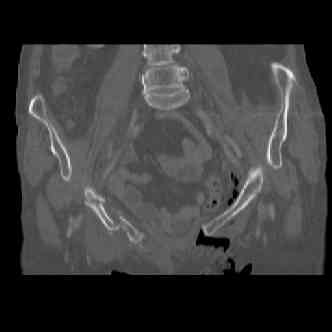

attached are several CT cuts. please let me know if you need more. the CT is pre-pelvic ex-fix placement.